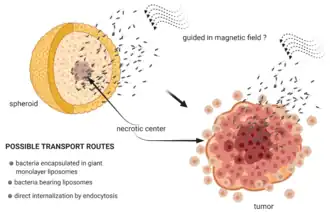

There are a variety of sensing, actuating, or pickup-and-delivery applications that scientists are currently aiming for, with local drug targeting for cancer treatment being one of the more prominent examples.[102][5] For applications like this, a micromotor needs to be able to move, i.e., to swim, freely in three dimensions efficiently controlled and directed with a reliable mechanism.[68]

The so-called biohybrid microswimmer can be defined as a microswimmer that consist of both biological and artificial parts, for instance, one or several living microorganisms attached to one or various synthetic parts. The biohybrid approach directly employs living microorganisms to be a main component or modified base of a functional microswimmer.[150][151] Initially microorganisms were used as the motor units for artificial devices, but in recent years this role has been extended and modified toward other functionalities that take advantage of the biological capabilities of these organisms considering their means of interacting with other cells and living matter, specifically for applications inside the human body like drug delivery or fertilisation.[152][153][68]

A distinct advantage of microorganisms is that they naturally integrate motility and various biological functions in a conveniently miniaturised package, coupled with autonomous sensing and decision-making capabilities. They are able to adapt and thrive in complex in vivo environments and are capable of self-repair and self-assembly upon interaction with their surroundings. In that sense, self-sufficient microorganisms naturally function very similar to what we envision for artificially created microrobots: They harvest chemical energy from their surroundings to power molecular motor proteins that serve as actuators, they employ ion channels and microtubular networks to act as intracellular wiring, they rely on RNA or DNA as memory for control algorithms, and they feature an array of various membrane proteins to sense and evaluate their surroundings. All these abilities act together to allow microbes to thrive and pursue their goal and function. In principle, these abilities also qualify them as biological microrobots for novel operations like theranostics, the combination of diagnosis and therapy, if we are able to impose such functions artificially, for example, by functionalisation with therapeutics. Further, artificial extensions may be used as handles for external control and supervision mechanisms or to enhance the microbe's performance to guide and tailor its functions for specific applications.[68]

Only a few decades later, microswimmers aiming to become true microscale surgeons evolved from an intriguing science-fiction concept to a reality explored in many research laboratories around the world, as already highlighted by Metin Sitti in 2009.[180][1] These active agents that can self-propel in a low Reynolds number environment might play a key role in the future of nanomedicine, as popularised in 2016 by Yuval Noah Harari in Homo Deus: A Brief History of Tomorrow.[181] In particular, they might become useful for the targeted delivery of genes [182] or drugs [183][184] and other cargo [185][186] to a certain target (e.g. a cancer cell) through our blood vessels, requiring them to find a good, or ideally optimal, path toward the target avoiding, e.g., obstacles and unfortunate flow field regions.[156]

Already in 2010, Nelson et al. reviewed the existing and envisioned applications of microrobots in minimally invasive medicine.[187] Since then, the field has grown, and it has become clear that microswimmers have much potential for biomedical applications.[1] Already, many interesting tasks can be performed in vitro using tailored microswimmers. Still, as of 2020, a number of challenges regarding in vivo control, biocompatibility and long-term biosafety need to be overcome before microswimmers can become a viable option for many clinical applications.[188][1]

A schematic representation of the classification of biomedical applications is shown in the diagram on the left below. This includes the use of microswimmers for cargo transport in drug delivery and other biomedical applications, as well as assisted fertilisation, sensing, micromanipulation and imaging. Some of the more complex microswimmers fit into multiple categories, as they are applied simultaneously for e.g., sensing and drug delivery.[1]